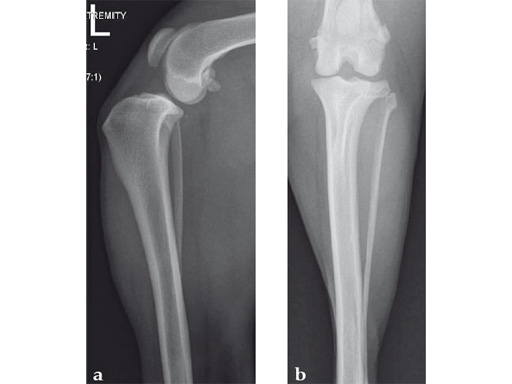

An 11-year-old female, spayed, 13.6 kg cocker spaniel had a complete tear of the left cranial cruciate ligament. A 2.4 mm TPLO plate was perfect for this dog due to the excessive slope of the tibial plateau (30) and the size of the dog. Three 2.4 mm locking screws were used proximally and three 2.4 mm cortical screws were used distally. The contour of this plate matches the contour of the bone almost perfectly. The plate is also designed to optimize the angle of the proximal screws so that they engage the most dense and thickest bone and avoids penetration of the stifle joint.